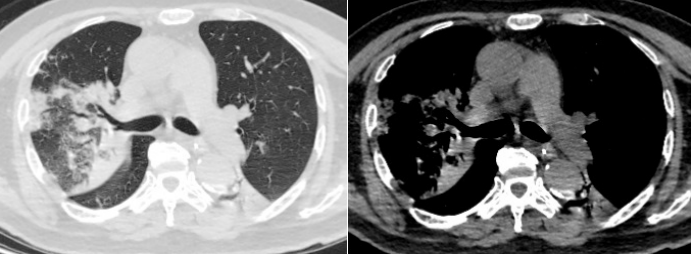

胸部CT(2025-04-23):右肺中上叶渗出,部分实变。右主支气管及右肺上叶支气管内多发黏液栓形成;两肺多发索条影;纵隔内稍大淋巴结;主动脉、冠状动脉硬化(图1)

1  患者入院胸部CT2025-04-23)